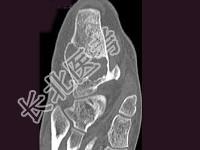

- 单项选择题男,32岁, 几天前踝部扭伤,疼痛, 不能行走,结合CT图像, 最可能的诊断是 ( )

A、骨囊肿

B、动脉瘤样骨囊肿

C、骨纤维异常增殖症

D、骨巨细胞瘤

E、畸形性骨炎